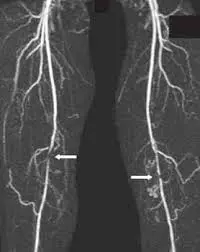

Angiotomografía (AngioTAC) en Caracas: Información, Precios y Beneficios La angiotomografía o AngioTAC es un procedimiento avanzado de diagnóstico por imágenes